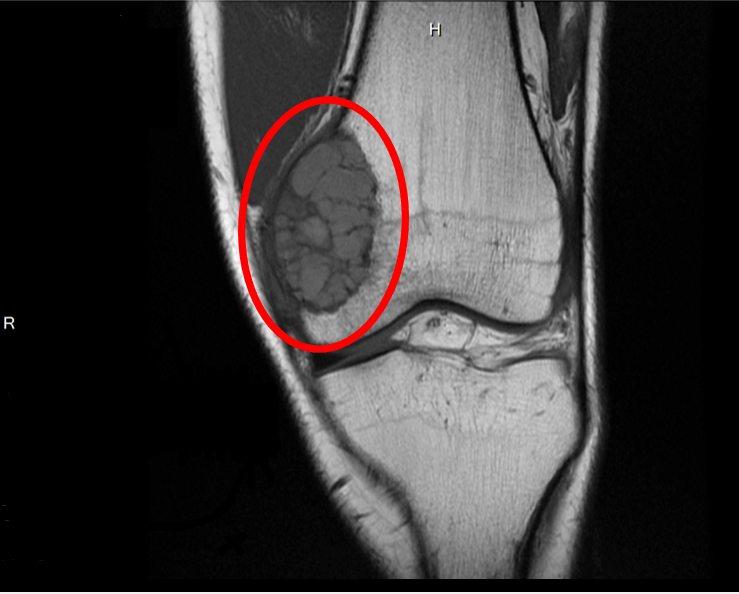

روش های عکس برداری می توانند به تعیین محل و اندازه ی تومورهای استخوان و گسترش یا عدم گسترش آن ها به سایر نقاط بدن کمک کنند. در این مقاله با علائم سرطان مغز استخوان و نیز روش های درمان آن آشنا می شوید. یک تومور رشد غیر طبیعی بافت در بدن است. سلول های توموری توانایی تنظیم کردن ندارند بنابراین سلول های بیشتری تولید می کنند و منجر به تشکیل یک توده می شوند در حالی که بسیاری از تومورها سرطانی.

تشخیص سرطان استخوان. استئوسارکوم شایع ترین نوع است که بیشتر بر کودکان و نوجوانان زیر 20 سال تأثیر می گذارد. جراحی اغلب اولین انتخاب درمانی می باشد اگرچه گاهی اوقات قطع کردن عضو لازم می باشد. درمان سرطان استخوان به نوع سرطان بستگی دارد.